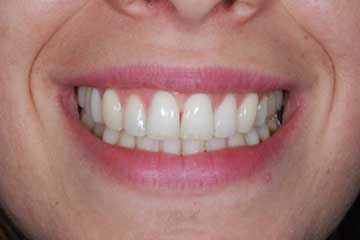

Con protesi fissa superiore e protesi fissa inferiore

I denti irrecuperabili dell'arcata superiore ed inferiore del paziente di anni 65

sono stati sostituiti da 10 impianti, cioè protesi radicolari endo-ossee che sostengono le protesi fisse superiore ed inferiore.